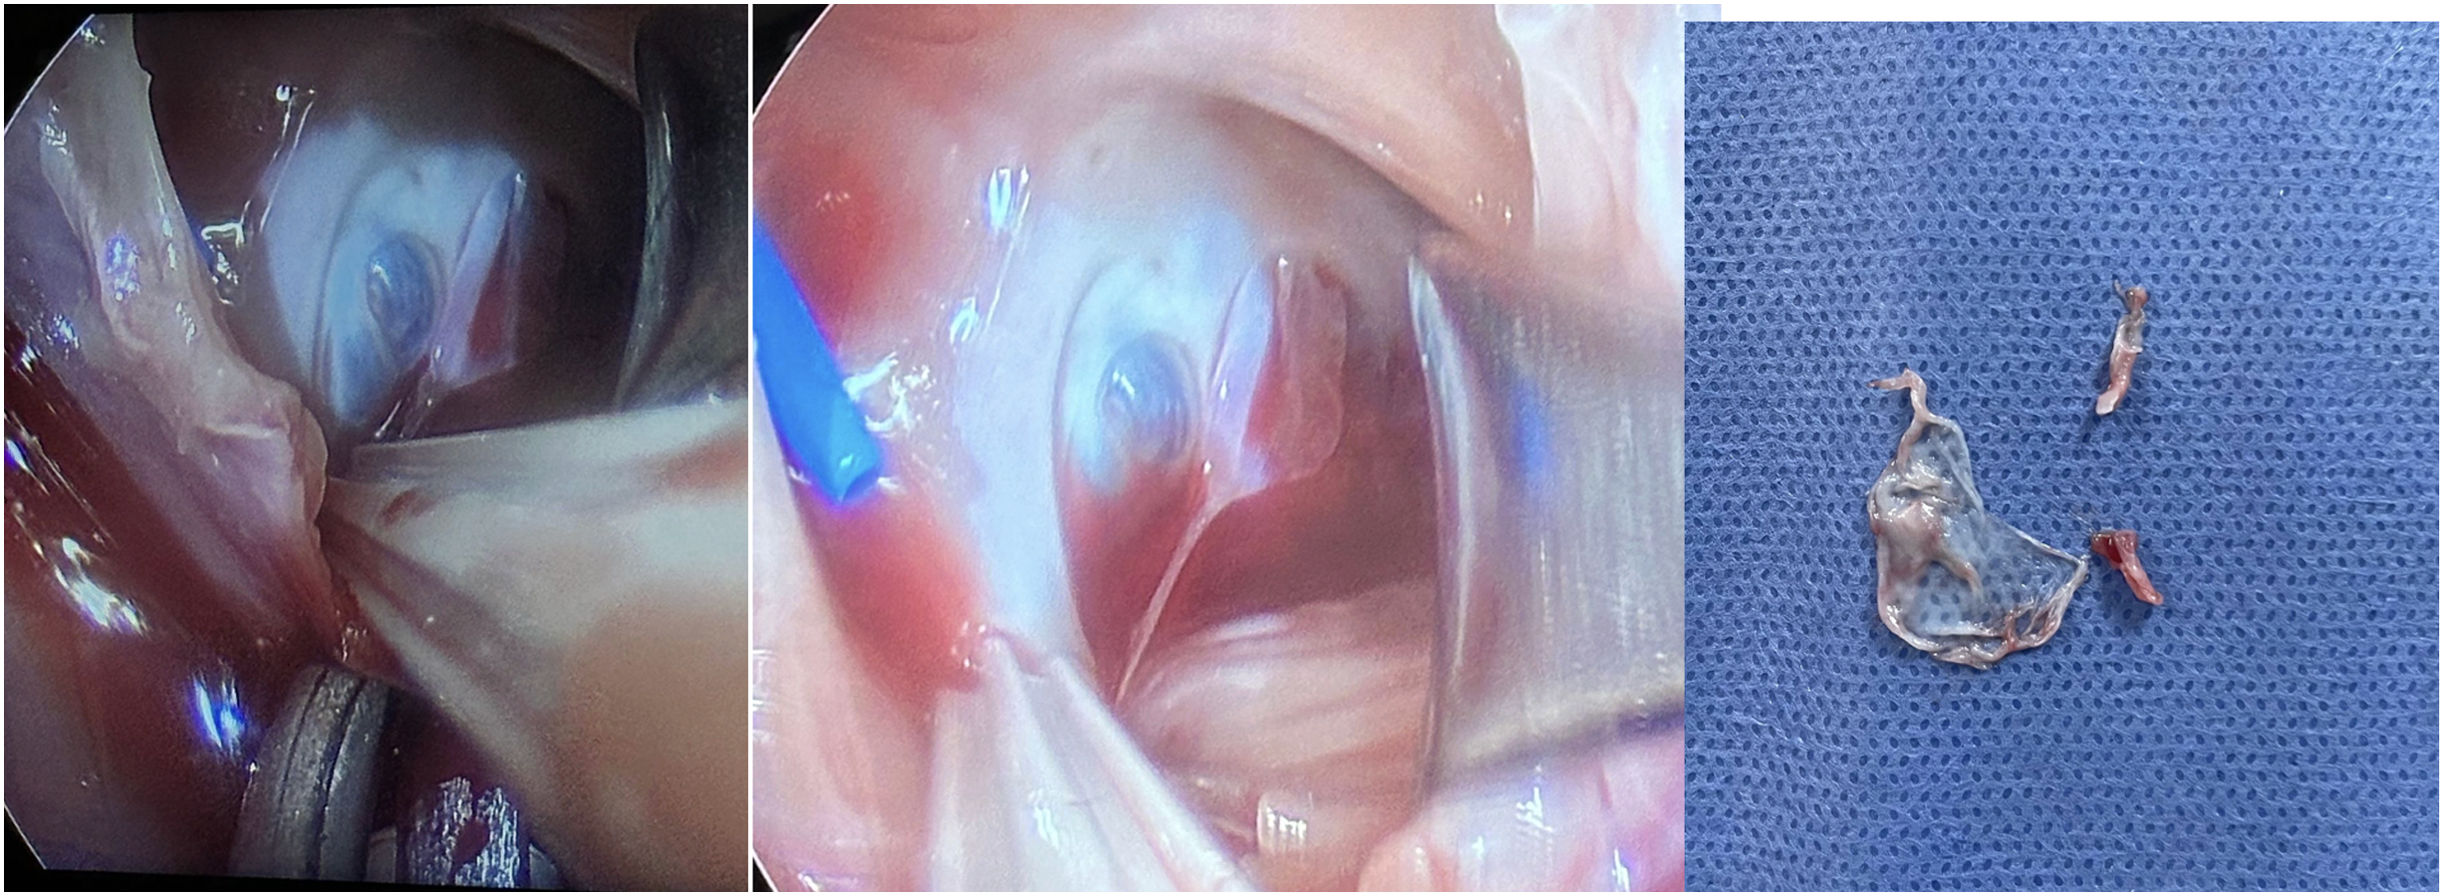

Por medio de mini toracotomía anterior periaerolar extendida en 4to espacio intercostal se realiza canulación aortica y de venas cavas y posteriormente se realiza auriculotomía derecha observando un quiste simple roto adyacente al seno coronario (fig. 2), se resecan paredes y pedículo, se cierra miocardio resecado con prolene 5-0. Tiempo CEC 44 minutos, pinzamiento 36 minutos. El paciente sale en ritmo sinusal, sin apoyo aminérgico ni ventilatorio invasivo egresándose a las 96 horas posquirúrgicas. El reporte histopatológico confirma quiste sanguíneo.